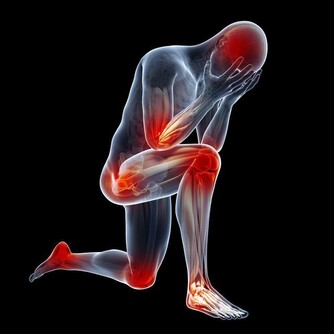

但剩下2/3症狀可能會愈來愈糟(約3成患者會惡化成乾癬性關節炎),

且必須一直持續治療,嚴重的話甚至會無法行走。

醫師建議乾癬患者務必注意關節症狀,像是早上起床,

關節紅腫脹痛特別明顯的人最好趕緊就醫,以免惡化至關節變形,造成不可挽回的悲劇。

2. 好發頭皮與肘膝:乾癬最常發生在頭皮、手肘、膝蓋等部位,

因為頻繁摩擦,導致皮膚會紅、變厚,而且有屑屑。